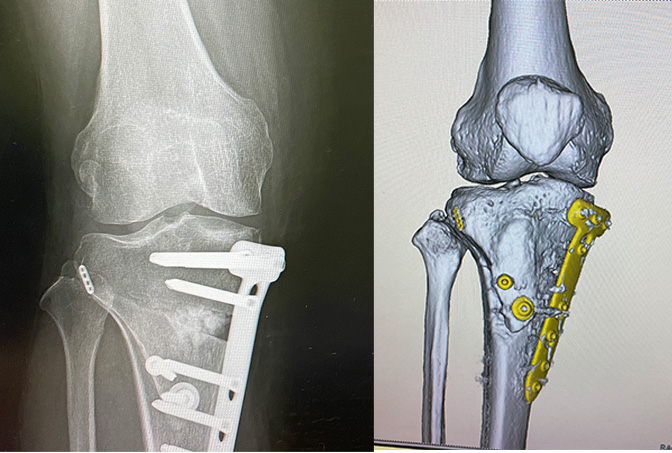

半月板損傷は放っておいても治らないとの話でしたので、治療方法に高位脛骨骨切り術(HTO手術)を提案されました。

なんでも、半月板を縫うと同時にO脚を外科的手術(高位脛骨骨切り術)で矯正するとか。

左:X線、右:CTスキャン

上の図のプレートを外す抜釘手術のために再入院しました。